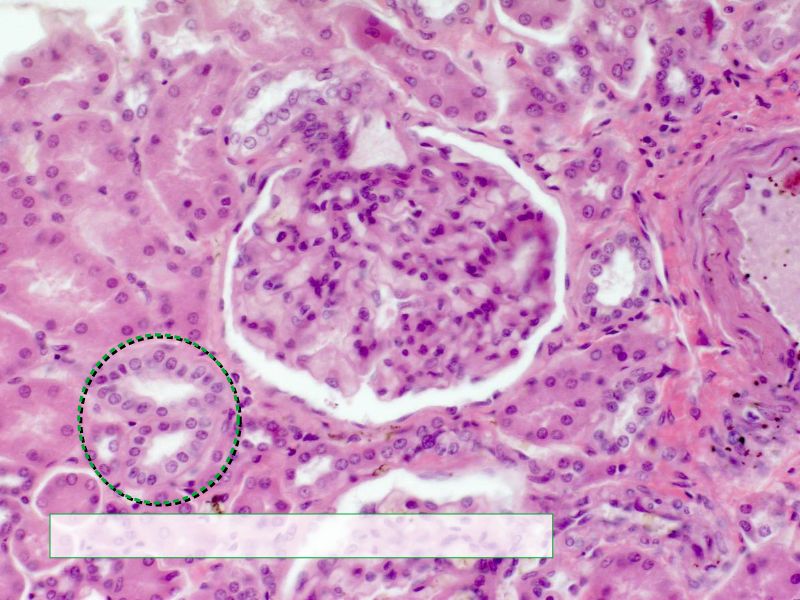

Proximal convoluted segment

- Longest part of nephron

- Wide triangular cell

- Spherical nucleus

- Indistinct cell borders

- Luminal surface

- Striated brush border

- Cuboidal epithelium

- Light stained

- Wide looking lumen

- Indistinct borders

Collecting tubule

- Cuboidal to columnar epithelium

- Distinct lateral borders